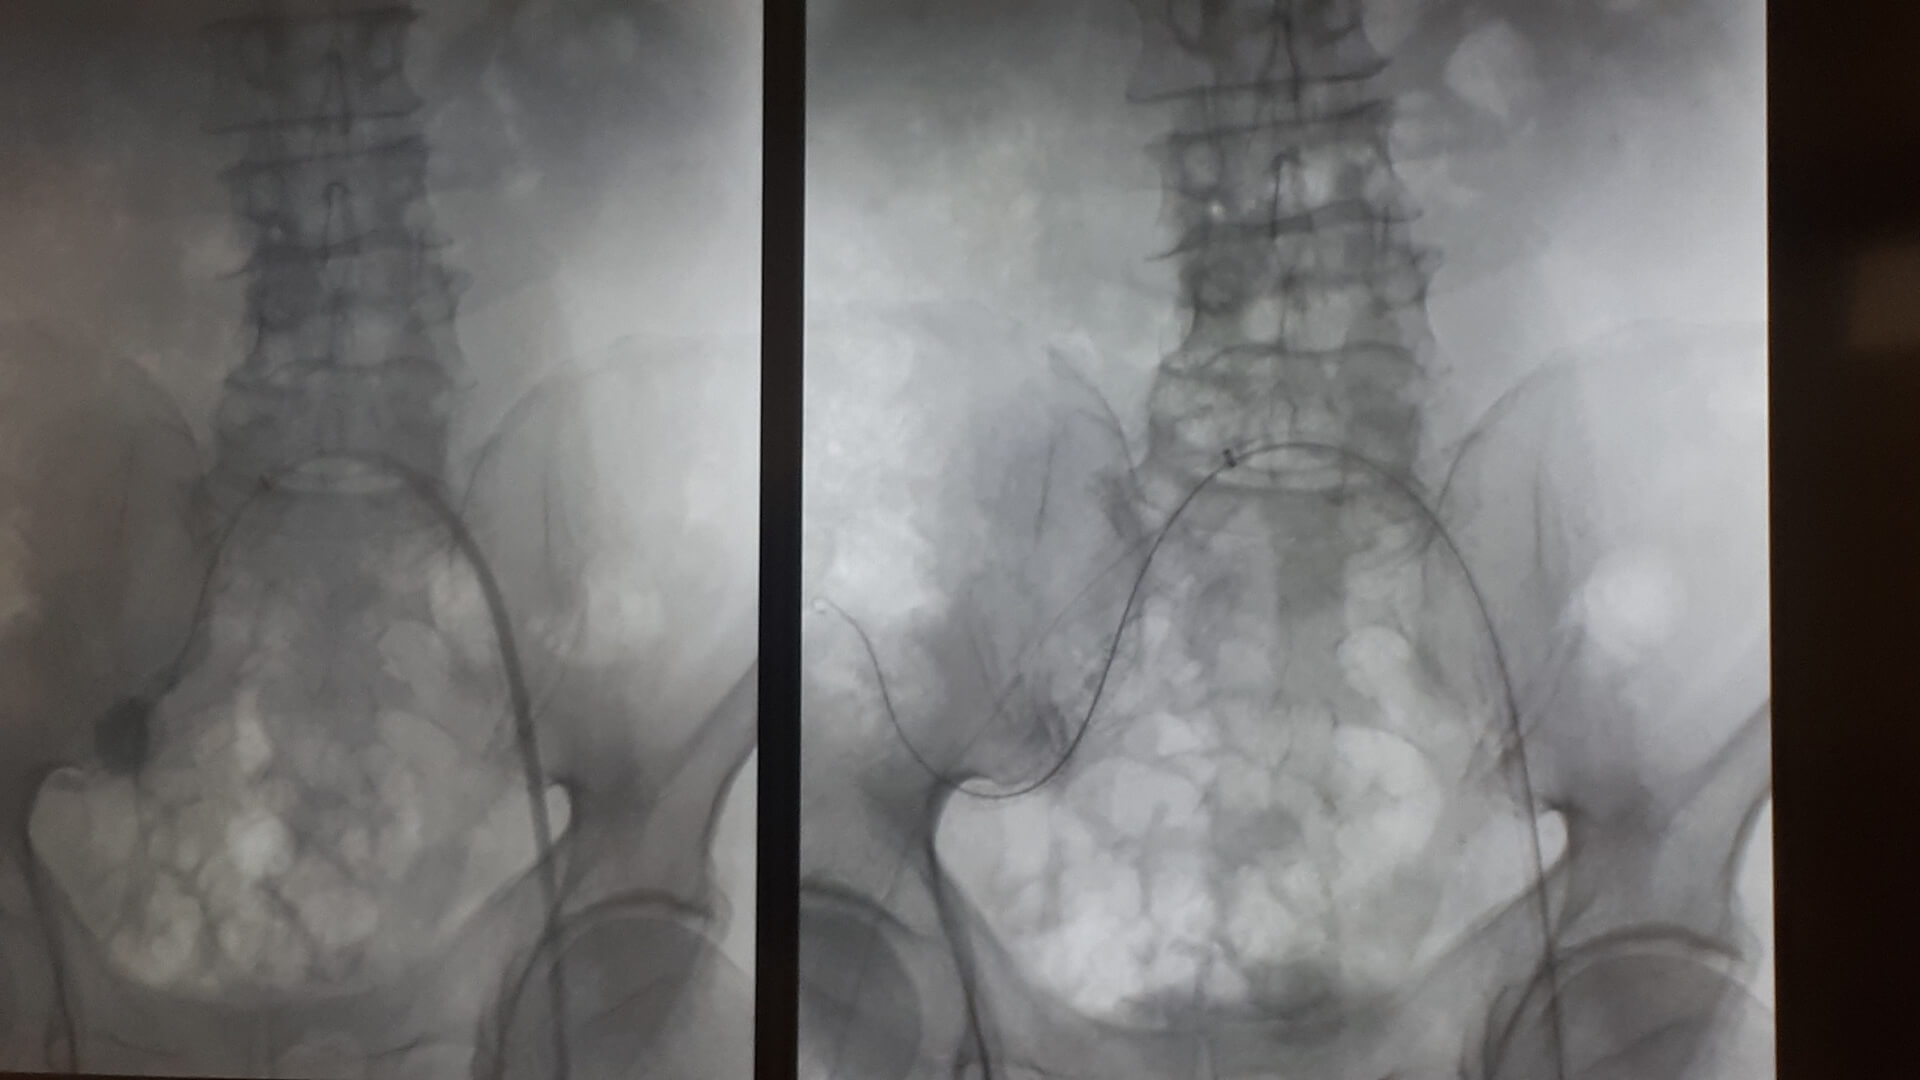

Pierwszą w Polsce operację wszczepienia nowego rodzaju stentgraftu, czyli specjalnej protezy do zabezpieczania tętniaków aorty, przeprowadzili lekarze z Uniwersyteckiego Szpitala Klinicznego w Białymstoku.

Chodziło o tętniaka tętnicy biodrowej u 64-letniego pacjenta. Operację przeprowadzono w minioną środę (10.04) w Klinice Chirurgii Naczyń i Transplantacji USK. Pacjent czuje się dobrze i niedługo wychodzi ze szpitala.

Jak mówił w czwartek (11.04) na konferencji prasowej kierownik tej kliniki dr hab. Jerzy Głowiński, tętniak miał prawie 4 cm, co w relacji do wielkości tętnicy biodrowej wewnętrznej stanowiło duże zagrożenie, bo w każdej chwili ścianki naczynia krwionośnego mogły pęknąć, powodując – zagrażający życiu – krwotok wewnętrzny. - Możliwości uratowania byłyby naprawdę znikome – powiedział.

Nie wchodziła w grę klasyczna operacja

W przypadku tego chorego nie wchodziła w grę klasyczna operacja, bo tętniak znajdował się zbyt głęboko, by był możliwy do niego dostęp chirurgiczny. Dotąd zasadą postępowania w takiej sytuacji było podwiązywanie lub wyłączanie tętnicy (klejem lub specjalnymi spiralami). Dr Głowiński zwrócił uwagę, że choć ta tętnica nie ratuje życia, to poprawia komfort pacjenta, bo odpowiada za ukrwienie narządów jamy brzusznej oraz – co istotne jest u mężczyzn – za prawidłową erekcję.

Rozwiązaniem okazał się nowy rodzaj stentgraftu, czyli specjalnej protezy wszczepianej do tętnic. "Jest to stentgraft, który jest jednocześnie i miękki, i na tyle sztywny, że się do tego celu dobrze nadawał" – powiedział. Zwrócił przy tym uwagę, że stosowane już standardowo stentgrafty są albo sztywne, albo elastyczne i do zabezpieczenia tętniaka w takim miejscu się nie nadawały.

DrJerzy Głowiński wyjaśniał, że tętnica biodrowa jest stosunkowo mała i kręta, do tego jej średnica nie jest na całej długości taka sama. Nowy rodzaj stentgraftu składającego się z pierścieni naprzemiennie sztywnych i elastycznych dał możliwość "domodelowania" go w taki sposób, by na całym zabezpieczanym tętnicy odcinku był właściwie zainstalowany.

Do tego od wewnątrz stentgraft jest pokryty heparyną, co ma zapewnić jego długotrwałą drożność i zapobieganie zakrzepicy. - Zakładamy, że stentgraft posłuży pacjentowi również na długie lata – dodał kierownik Kliniki Chirurgii Naczyń i Transplantacji USK w Białymstoku. Przyznał, że takie umiejscowienie tętniaka jest rzadkie, w statystykach białostockiej kliniki trafia się 2-3 razy do roku. Zoperowany z użyciem nowego rodzaju stentgraftu pacjent czekał na to dwa miesiące. Sama proteza kosztuje ok. 9-10 tys. zł. Stosowane dotąd inne ich rodzaje są średnio dwa razy tańsze.